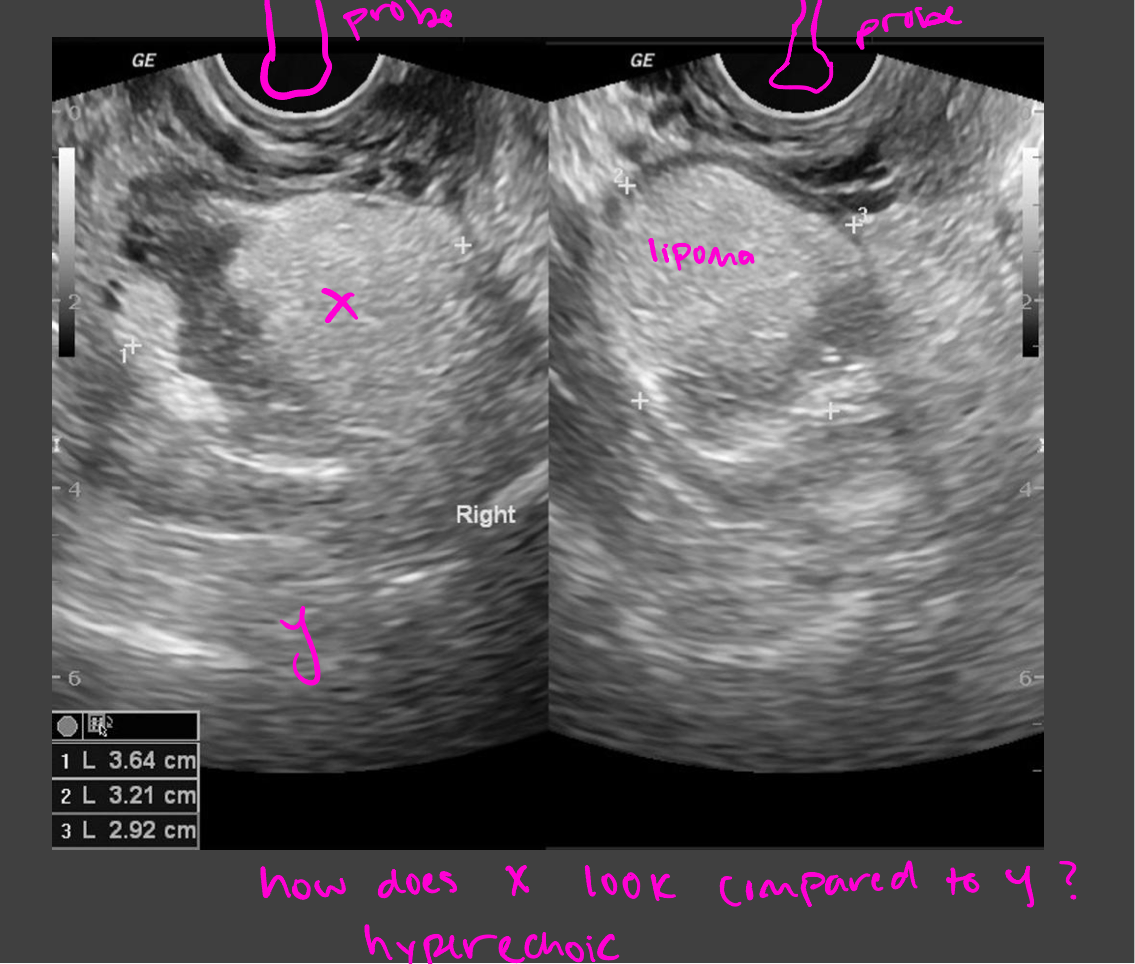

Echogenicity

Level of gray or brightness on an ultrasound image

Described in relation to surrounding tissues

Hypoechoic

abscesses, fatty tissue

Darker = less echoes

Hyperechoic

Bone, kidney/gallbladder stone

lighter = more echoes